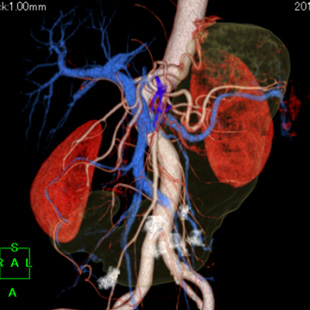

高精度画像診断技術

当院では、各種画像診断装置を導入し、主に各種悪性腫瘍を対象に画像診断、内視鏡的治療、画像介入性低侵襲治療(血管内治療など)、外科的治療に幅広く取り組んでいます。

目的に合った低侵襲な画像診断検査を行い、がんの早期発見および治療に努めています。